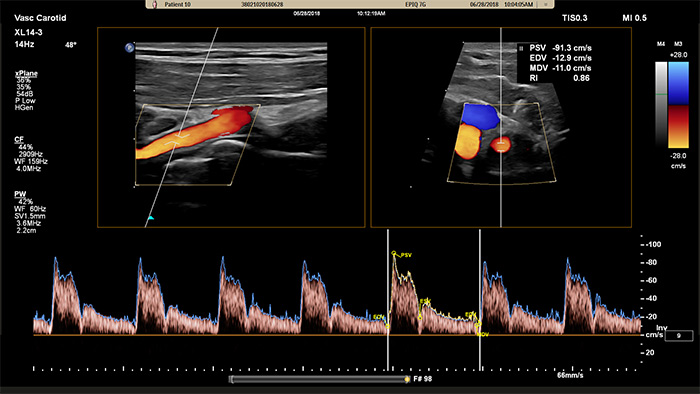

Der XL14-3 xMATRIX Schallkopf ermöglicht eine xPlane Bildgebung, die über den herkömmlichen Ansatz bei Gefäßuntersuchungen hinausgeht und Echtzeitbilder gleichzeitig sowohl in der Längs- als auch Querebene bereitstellt. Wichtigster Vorteil: Bei der xPlane Bildgebung muss der Schallkopf zur Erfassung orthogonaler Ansichten nicht mehr rotiert werden. Mit einer einfachen Bewegung des Trackballs ist eine vollständige anatomische Beurteilung möglich – und die Untersuchungsdauer wird verkürzt.

Der XL14-3 xMATRIX Schallkopf verfügt zudem über xPlane Doppler-Funktionen. Im xPlane PW-Doppler-Betrieb lässt sich das Doppler-Probenvolumen anhand der Referenzbilder in der Längs- und Querebene präzise platzieren. Wichtigster Vorteil: xPlane Doppler reduziert Platzierungsfehler bei Probenvolumen und führt bei der Untersuchung größerer Stenosen zu einer besseren Reproduzierbarkeit und Konstanz.